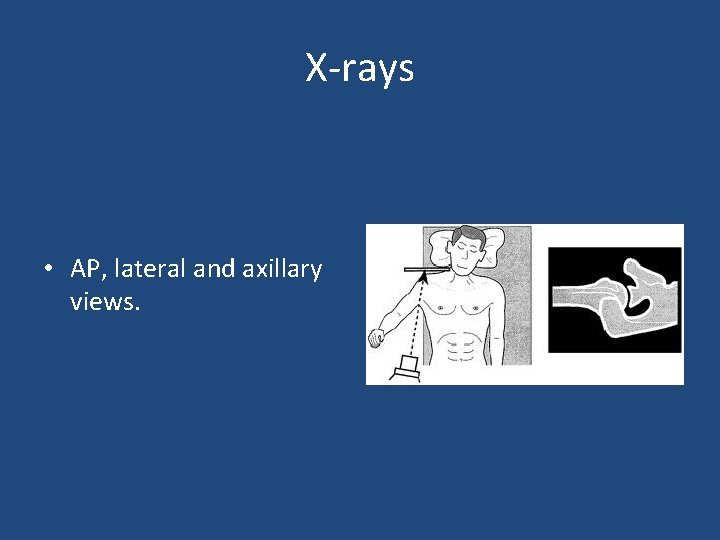

X-rays • AP, lateral and axillary views.